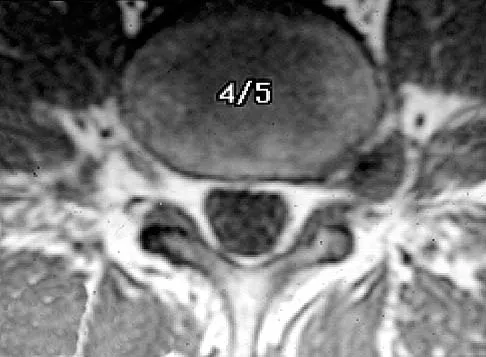

An Asian 45-year-old man has bilateral upper extremity dysfunction. Figure 35a shows a T2-weighted sagittal MRI scan of the cervical spine, and Figure 35b shows a T2-weighted axial MRI scan at the level of the C3 vertebral body. What is the most likely pathologic process?

Explanation